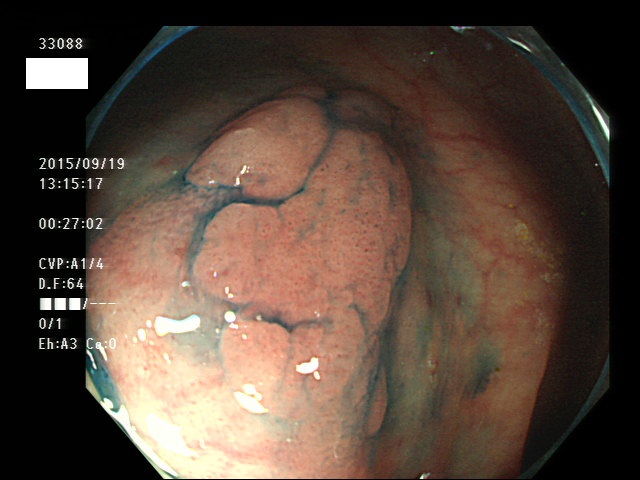

上記100名より抽出した平坦・陥凹型腺腫(=癌化の危険が高いが見落としやすい病変)の内視鏡写真

33003 33004 33005 33006 33007 33008 33009 33010 33011 33012 33013 33014 33015 13306 33018 33021 33024 33025 33026 33029 33030 33031 33032 33033 33036 33038 33039 33041 33042 33045 33046 33048 33051 33053 33054 33055 33057 33060 33063 33066 33068 33069 33071 33072 33074 33077 33078 33080 33086 33088 33089 33090 33091 33093 33095 33096 ・・・・・・の56名